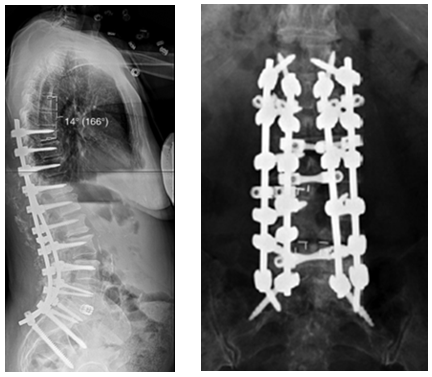

T10骨盆固定,出现交界性后凸

行翻修手术:T9/10SP截骨,延长到T4固定,预防性双侧肋骨固定(VEPTR)

图32-33 肋骨固定